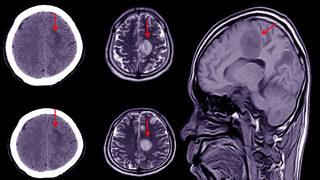

Hidrosefali haberleri sayfası, bu önemli sağlık durumu hakkında en güncel ve doğru bilgileri sunmayı amaçlar. Hidrosefali, beynin içindeki sıvının anormal birikmesiyle karakterize edilen bir rahatsızlıktır ve hastalar için ciddi sağlık sorunlarına yol açabilir. Son dakika hidrosefali gelişmeleri ile bu konudaki en son araştırma ve tedavi yöntemlerini takip edebilirsiniz.